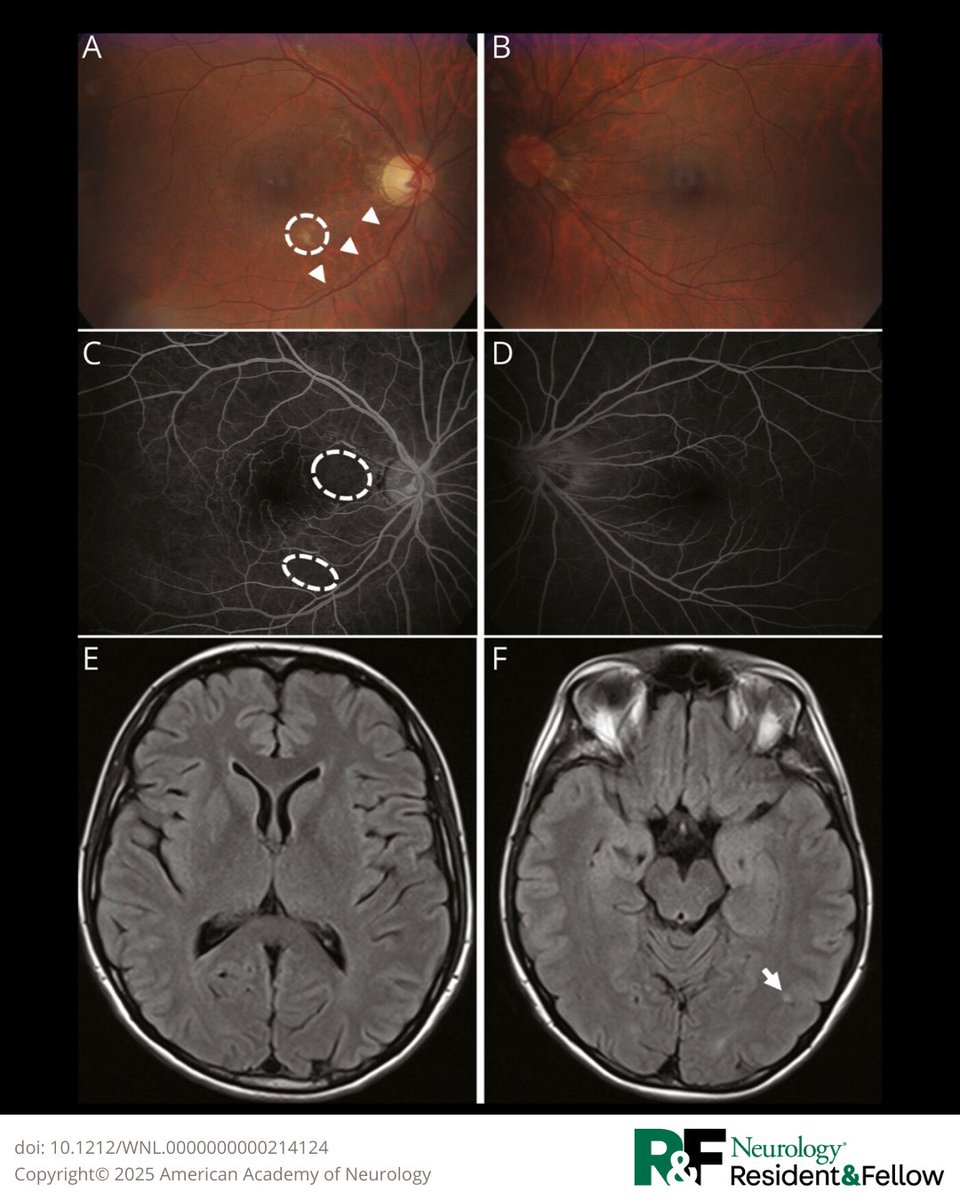

Pearls & Oy-sters: Adult-Onset Coats Plus: A Case of Leukoencephalopathy With Calcifications, a Tumefactive Brain Lesion, and a Presumed Autoimmune Disease hubs.la/Q03KbtX10 #NeurologyRF

Pearls &amp; Oy-sters: Adult-Onset Coats Plus: A Case of Leukoencephalopathy With Calcifications, a Tumefactive Brain Lesion, and a Presumed Autoimmune Disease